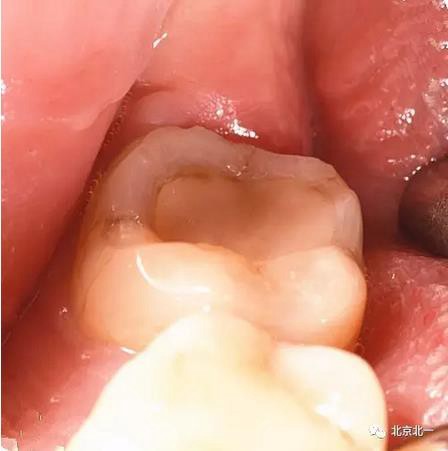

圖五:臨床所見